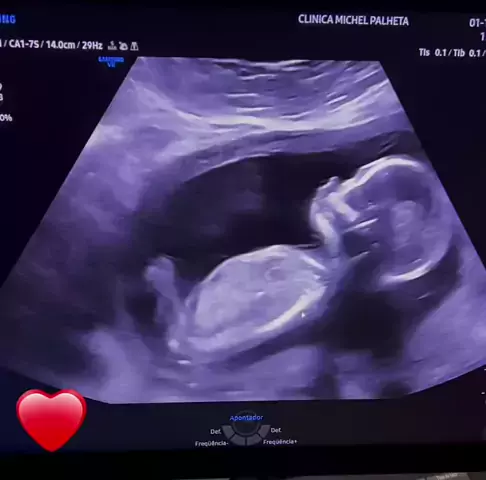

Triste notícia #gravidez #ultrassom #anencefalia #mãe #tragedia